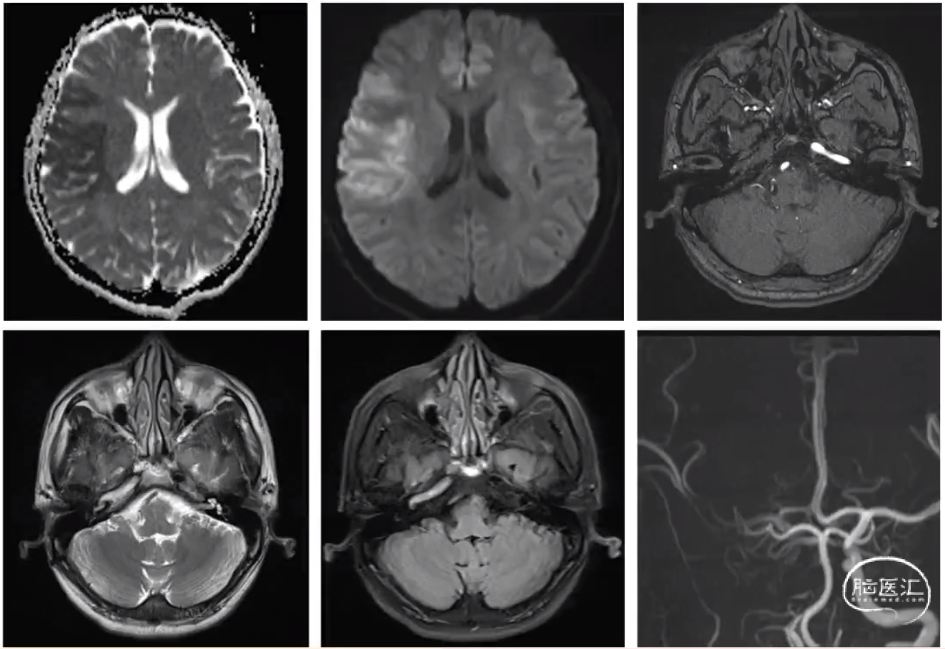

患者男,20岁,因“头晕伴恶心呕吐半小时余”入院。既往体健。查体NIHSS评分1分(面舌瘫1分)。

右侧小脑半球及背侧丘脑异常信号,考虑急性脑梗死

右心声学造影描述:自右肘中静脉注射生理盐水,右房、右室顺序显影,随呼吸左房、左室内可见造影微泡,微泡数量>30个/帧;嘱患者Valsalva动作后,左心房造影微泡明显增多。

诊断:右心声学造影提示房水平存在右向左分流(Ⅲ级)